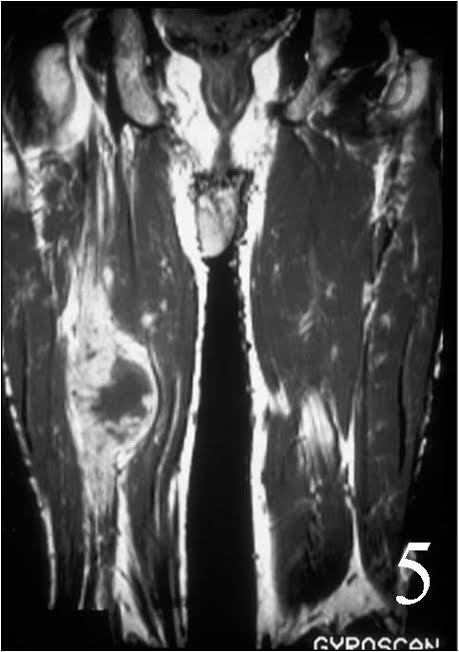

- With gadolinium (Fig. 4, 5)

- Reverse target post-contrast

- Increased gadolinium uptake——->unlike peripheral nerve sheath tumor (PNST)

MRI of the thigh, showing a heterogeneous soft tissue lesion in the posterior compartment of the thigh on axial (Fig. 2) and coronal (Fig. 3) T1W images. The addition of gadolinium contrast shows enhancement in the periphery of the mass with necrosis and hemorrhage in the center of the mass typical of a high grade sarcoma (Fig. 4 and 5)